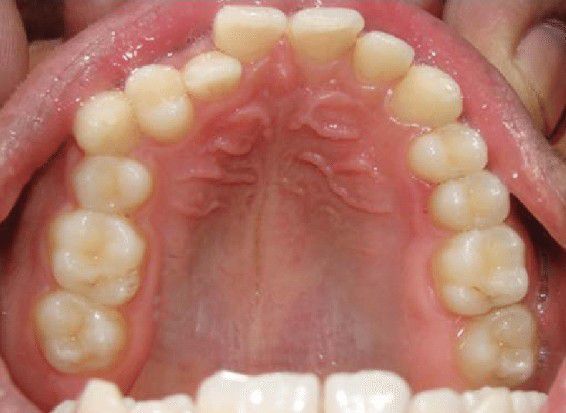

Transposition of Canine With 1st premolar

Transposition is defined as an interchange in the position of two permanent adjacent teeth located at the same quadrant in the dental arch